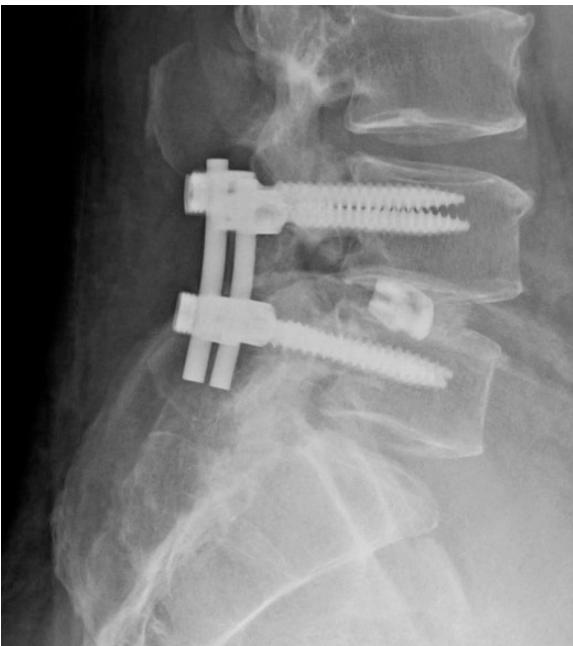

Degenerative Spondylolisthesis

- Definition: Common degenerative condition characterized by subluxation of one vertebral body anterior to the adjacent inferior vertebral body with intact pars

- Demographics: Most common in females over 40 years of age, at the L4-5 level

- Diagnosis: Lateral radiographs; flexion and extension lateral lumbar radiographs can identify degree of instability

- MRI: Helpful for central or foraminal stenosis

- Nonoperative: Trial with NSAIDs and physical therapy

- Surgical: Indicated for progressive disabling pain that has failed nonoperative management, and/or progressive neurological deficits